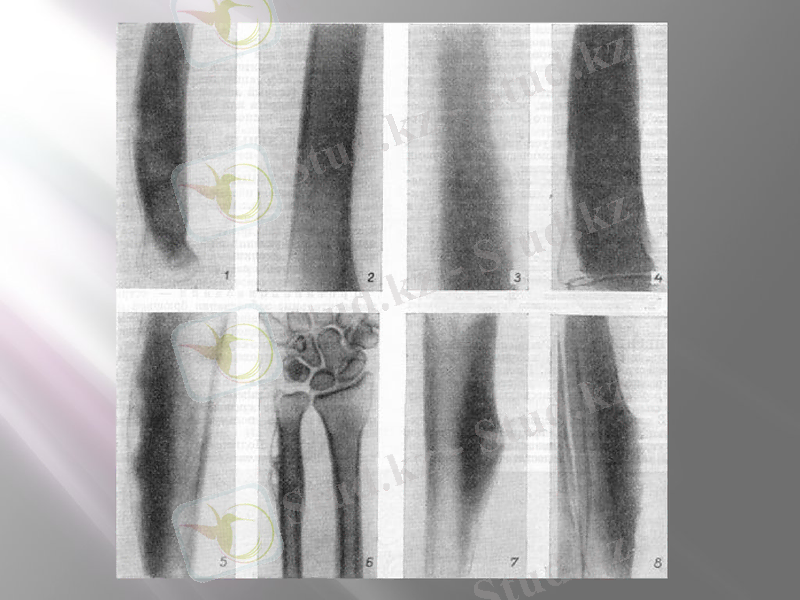

Iрiңдi периостит. (Periostitis purulenta) - ашық сүйек сынғанда, сүйектiң сыртқы қабығы iрiңдеп, көбiнесе стафилакоктi, стрептококтi инфекциялар айналасындағы қабынған iрiңдi қоспалардан, қаннан өтедi.

Клиникалық белгiлерi. Iрiңдi периостит жалпы, ауыр және жергiлiктi түрінде қабынулары болады. Организмнiң нашарлауы дене температурасының жоғарлауына, пульстiң жиiлеуiне, тыныстың бұзылуына, бiртiндеп және толығымен азықтан бас тартады.

Бастапқы сатысында жергiлiктi реакциясы көрiнедi айқын және коллатеральды iсiнулер байқалады; зақымданған ұлпалардың орны тығызданады, ауырсыну реакциясы байқалады. Сүйек бетi iрiңдегенде, iрiң iшiне қарай ығысады, ал оны ашқаннан кейiн iрiңдi тесiк пайда болады. Iрiңдi тесiктi тексергенде сүйек бетiнде бұжыр немесе секвесторды анықтауға болады. Егер осы қабыну процесi аяқта болса, тұяқтың толық түсуiне, немесе аяқтың күштi ақсауына алып келедi.

Фиброзды периостит (Periostitis fibtosa) - сүйек үстінде фиброзды байланыс ұлпасының өсуiмен сипатталады. Фибриозды периоститтер сүйектiң дистальды бөлiмiнде жиi кездеседi. Сүйектiң қайталанып соққы алуынан, сүйектiң ұлпалары мен тамырлары, сiңiр байланыс ұлпаларын тiтiркендiруiмен, қабыну процессi созылмалы түрге айналады.

Клиникалық белгiлерi. Зақымдалған сүйектi терең пальпациялағанда терi астында және жұмсақ ұлпаларда температурасы жоғарламайтын аз ауырсынатын тығыз iсiнулер пайда болады. Фибринозды периоститте терi бетi жеңiл қозғалады. Организмнiң бұзылыстары фибринозды периоститтер iрi қантамырлар, жүйке жүйесі, сiңiрге, сонымен қатар буындарға жақын аймаққа орналасқанда әсерiн тигiзедi.

Оссифирленушi периостит. Сүйек ұлпасының өсуi, көбейуi қабынған сүйек беттерiнен басталады. Фиброзды периоститте сүйек сыртқы қабығының қабынуы iшiнен де, сыртынан да басталады. Сүйек үстінiң сыртқы және iшкi қабынулары, негiзiнен механикалық фактордан iшкi қабынулардан болады (зақымданулар, сынықтар, сүйектiң жарылулары, буынның дистрозиясы, көбiне байламдардың сүйекке бекiтiлген жерiндегi жыртылуы) және қабыну процестерiнiң жақын орналасқан ұлпалардағы абцесстен, флегмонадан, жаралардың асқынуынан болады. Оссифицирленген периоститке мал аяқтарының маймағы, ауыр жұмыстар қатты әсерiн тигiзiп, ет, сiңiр, байлам ұлпаларының зақымдануына септiгiн тигiзедi.

Клиникалық белгiлерi. Сүйектiң зақымдалған аймағын терең пальпациялағанда шеттерi шектелген, тығыз, бетi тегiс, температурасы жоқ қызарған iсiнулер тiркеледi. Периостит бетiндегi терi жеңiл қозғалады. Фиброзды периоститте қан, лифа тамырларының, жүйке жүйелерiнiң, сiңiрлердiң, буындардың шоғырланған тұсында қатты ауырсыну байқалады.